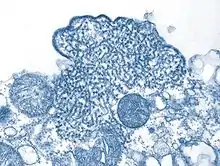

![]() | |

| Structure of a Henipavirus | |